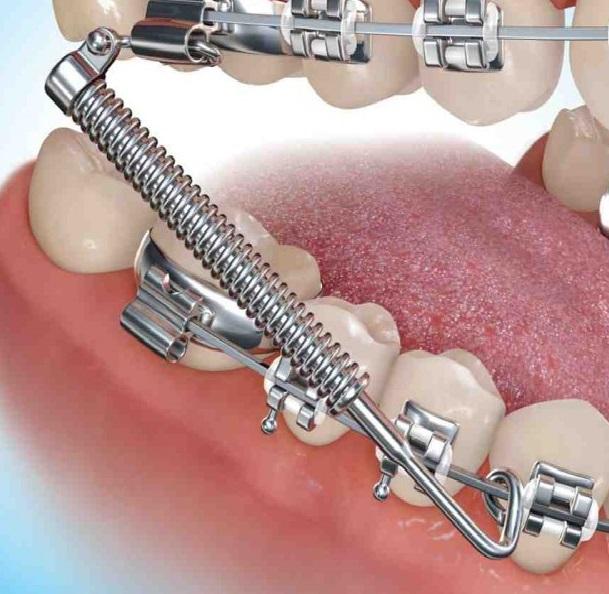

Class II correctors are metal push rod spring that are attached to the brace from the upper jaw to the lower jaw. These cannot be removed by the patient and put a constant gentle force on the teeth to help to move them into proper alignment during orthodontic treatment These help to correct the way a person bites by pulling the top teeth back and pushing the bottom teeth forward.